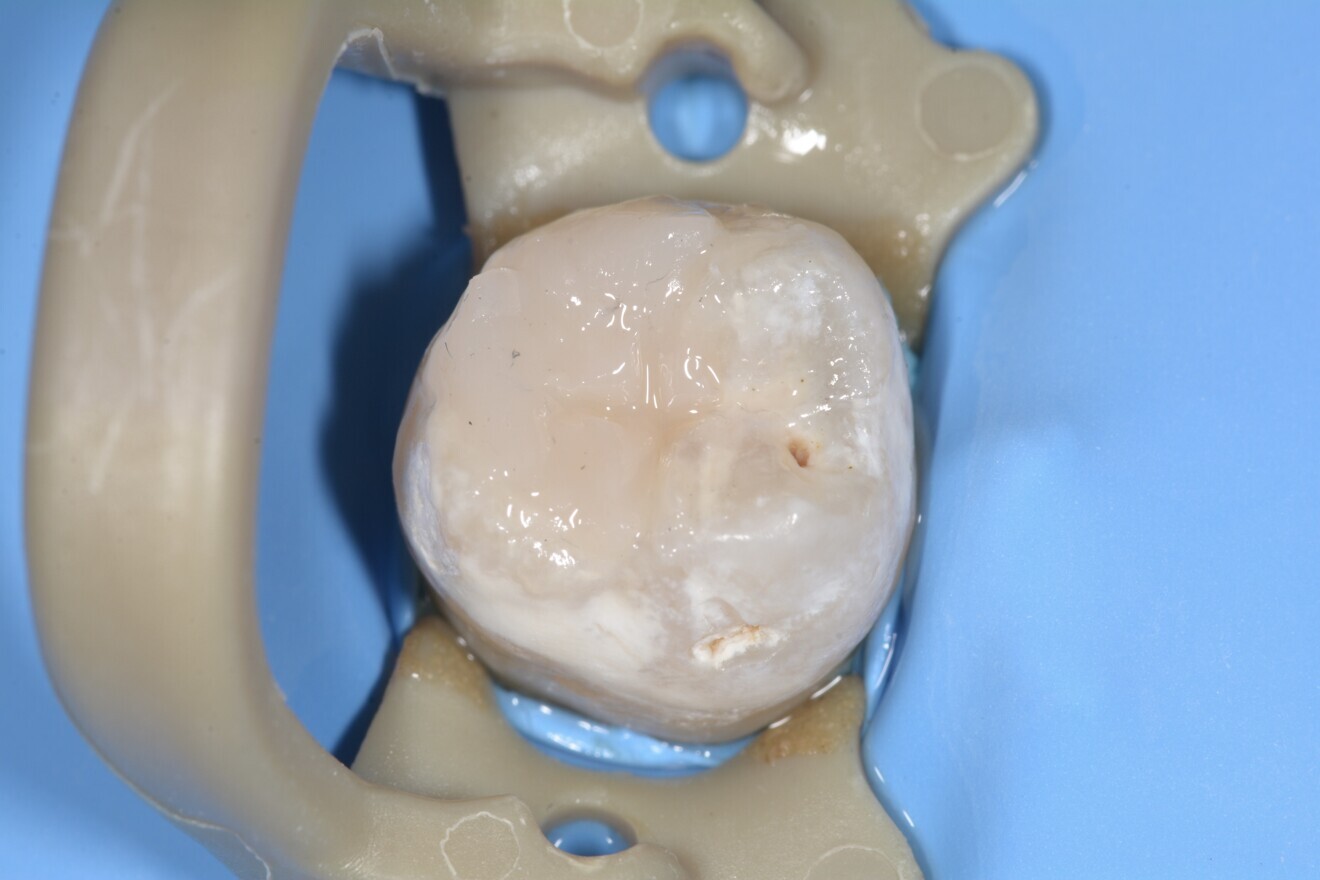

Fig. 16 : Reconstitution terminée.

Dans le cadre de l’approche Bio-Bulk Fill, une cartouche de Biodentine XP 00 (Fig. 12) a été appliquée dans la cavité et laissée en place sans y toucher pendant 10 à 12 minutes (Fig. 13). Un système adhésif auto-mordançant a ensuite été placé, conformément aux instructions du fabricant à l’aide d’une micro-brosse, sur les parois de la cavité ainsi que sur Biodentine. La monocouche adhésive a ensuite été polymérisée pendant 20 secondes. La partie occlusale amélaire de la cavité est restaurée à l’aide d’une fine couche de composite fluide photo polymérisable, suivie d’un composite microhybride. Après polymérisation finale, la restauration est sculptée et polie à l’aide de fraises diamantées fines et de pointes abrasives.